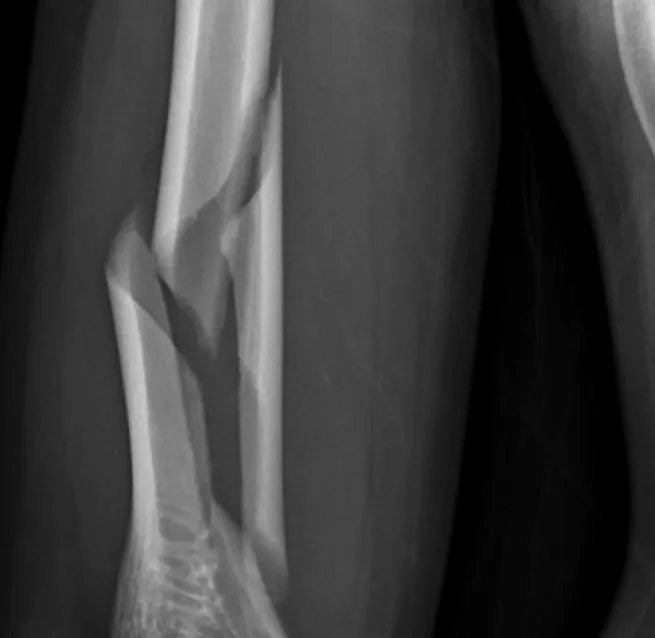

瘦高男注意!他比腕力竟把手臂擰斷 扭轉力比撞擊更傷骨

肱骨螺旋性骨折

扭轉力骨折